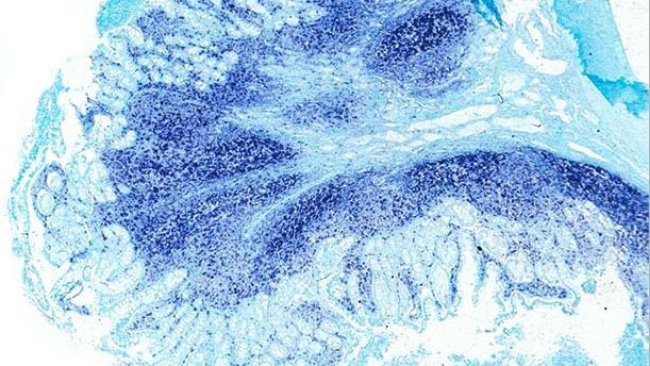

Comment le PCV2 contribue aux troublles intestinaux ?

Récemment on a émis l’idée que le PCV2 est capable de produire de la diarrhée chez les porcs et on a proposé la maladie entérique associée au PCV2 (PCV2-ED) comme une entité séparée à l’intérieur des maladies associées au circovirus porcin (PCVDs).